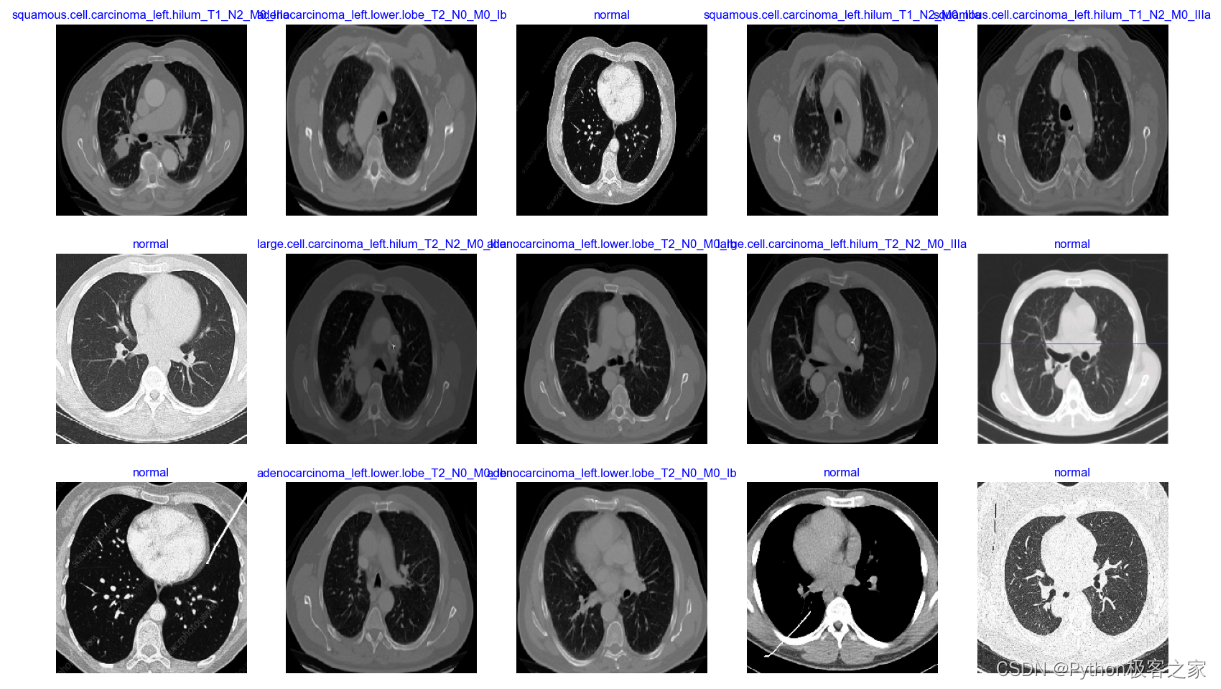

2. 肺癌CT影像数据读取

利用 TensorFlow 的 ImageDataGenerator 创建训练、验证和测试数据的生成器: